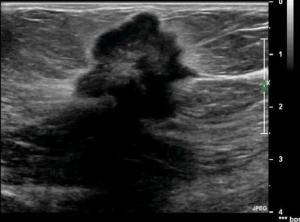

What many fail to recognize are the glaring inaccuracies associated with the ultrasound profession and the exams being performed on the television screen. Such scenes contain incorrect anatomy, probes placed in wrong positions, or actors who need more camera face time and scan patients backwards.